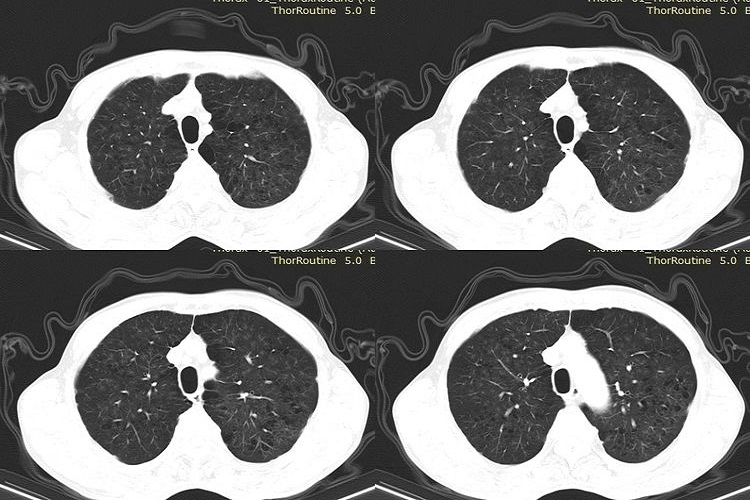

早期矽肺CT特征表现为双肺多发、无融合的小结节影,大小不等,多为2-5mm,位于小叶中心和胸膜下,可发生钙化。早期结节多位于上肺,但中、下肺也较常见,在CT上92.4%的病变分布于后肺野,肺内网状阴影不明显。